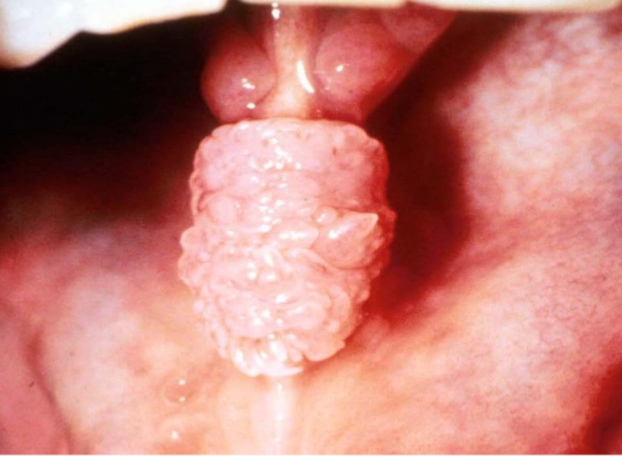

corrugated

small solid surface projections/elevations found in clusters